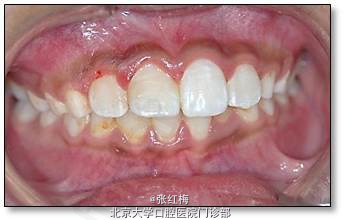

颜面左右对称;上唇正中见1×1cm2破溃面,其上覆黄白伪膜,周围粘膜略水肿

11牙冠龈1/3折断,牙髓暴露约6×1mm2,灰紫色,略有增生,叩(±),不松,龈未见异常,

21牙冠龈1/3釉质横形隐裂,叩痛(-),不松,冷测同正常对照牙,龈未见异常;

11、21正中牙合及前伸牙合未见明显牙合创伤;

处理:11去旧充填体,11及断片牙体预备(颊侧备斜面,髓腔备固位形,舌侧备排溢道),one-coat bond+纳米树脂粘接断冠,调牙合,抛光。